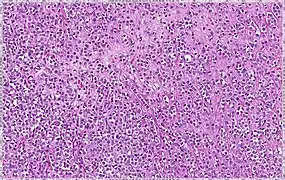

| Classical | 40% | Round or ovoid cells with little cytoplasm in a single-file infiltrating pattern, sometimes concentrically giving a targetoid pattern | ![]() |

| Pleomorphic | Classical-appearing but with pleomorphic cells. It may include signet-ring cells, or plasmacytoid cells (pictured) which have abundant cytoplasm and eccentric nuclei. | ![]() |

Invasive lobular carcinoma demonstrating a predominantly lobular growth pattern

Lobular breast cancer. Single file cells and cell nests.